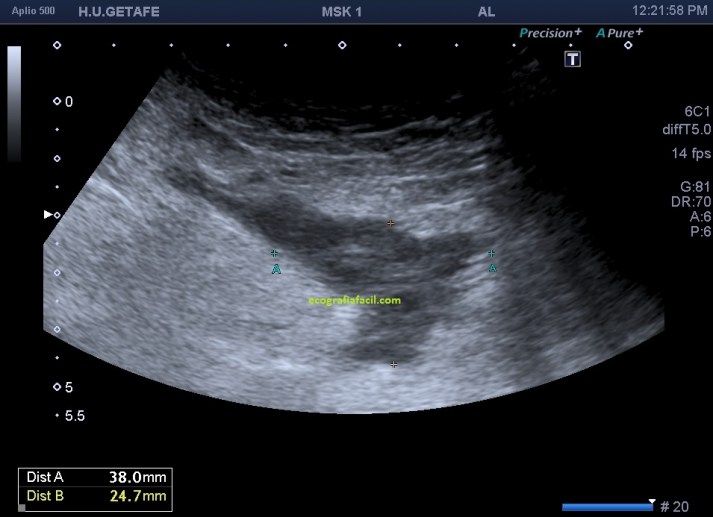

Es lo que ves en este otro caso, imagen 4, 5 y 6, donde se observan estos cambios que has visto en la primera parte de Post, pero además, aquí el caso es diferente, la etiología es distinta y en este caso, la paciente presentaba cambios en partes blandas y un gran absceso infeccioso en profundidad que requirió colocación de un drenaje.

El absceso era de tal calibre que debí usar vista panorámica (imagen 4) que evidenció una medida máxima de 11 cms, si no tienes este ajuste, puedes usar la sonda de baja frecuencia, que tiene peor calidad de imagen, pero permite medidas grandes (imagen 5).

5

El absceso presenta aspecto anecoico-hipoecogénico en profundidad, podemos verlos de tamaños distintos, este era grande y puedes ver en la imagen 6, como hay dos imágenes tubulares, hiperecogénicas con aspecto de cuerpo extraño que llegan hasta la colección líquida infectada comentada, mira: